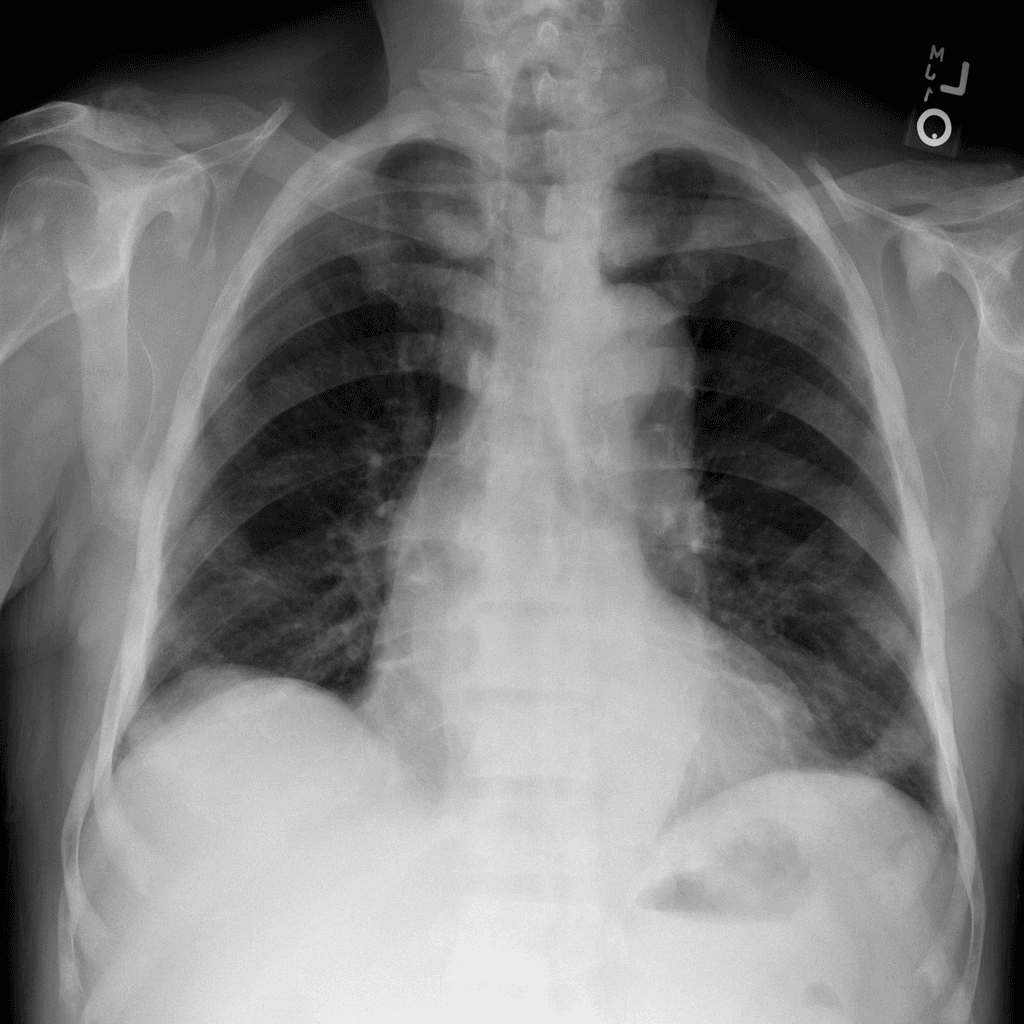

Detect Pneumothorax Using Chest X-ray Images

Leverage advanced AI algorithms to accurately identify Pneumothorax using Chest X-ray imaging. Our solution enhances diagnostic precision, enabling healthcare professionals to make timely and informed decisions for optimal patient care.